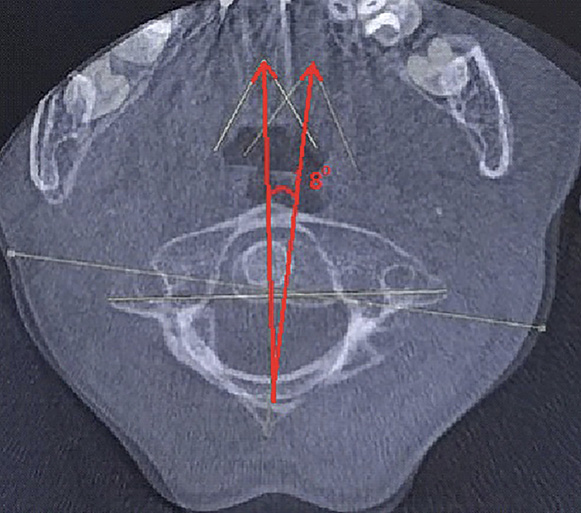

Для уточнения характера выявленных изменений в ручном режиме с помощью программы Adobe Photoshop© выполнено наложение аксиальных срезов 1-го и 2-го шейных позвонков, полученных по отдельности, с созданием единого изображения с возможностью комплексной оценки взаимоотношений изучаемых сегментов (рис. 2). При анализе смоделированного изображения обнаружено, что ротация атланта составляет 35° вправо (рис. 3). Суставные поверхности латерального атлантоаксиального сустава справа совпадают, а слева –суставная поверхность атланта смещена кпереди, что соответствует ротационному подвывиху типа II по классификации J. W. Fielding и R. J. Hawkins [8].

Рис. 2. Конусно-лучевая компьютерная томография краниовертебральной области. Аксиальные срезы на уровне аксиса (А) и на уровне атланта (Б). Стрелками обозначены передне-задние оси позвонков

Рис. 3. Наложение изображений А и Б, представленных на рис. 2. Определение угла ротации атланта

Было принято решение провести лечение в амбулаторных условиях, осуществляя устранение подвывиха с помощью бандажа для жесткой фиксации шейного отдела позвоночника, в виде постоянного ношения сроком на 7 дней. Кроме этого, был проведен курс лечебной гимнастики под контролем врача по лечебной физической культуре. По данным контрольного исследования КЛКТ, выполненной через 7 дней, отмечалась положительная динамика в виде уменьшения угла ротации атланта до 8° и восстановления конгруэнтности суставных поверхностей латерального атлантоаксиального сустава слева (рис. 4).

Рис. 4. Наложение изображений атланта и аксиса в аксиальной плоскости на контрольном исследовании после лечения